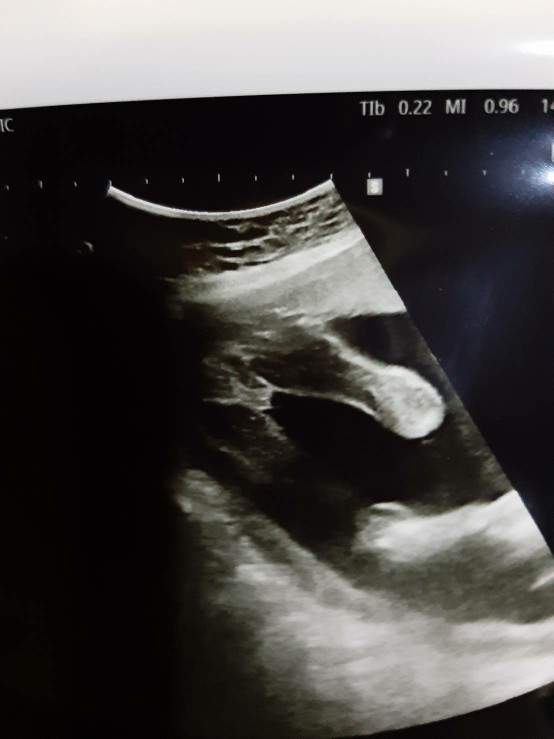

รู้เพศตอน18วีคครับเพศชาย

บ้านนี้ 12 week.จู๋โด่เลยจร้า

บ้านนี้รู้ตอน 17 วีคจ้า